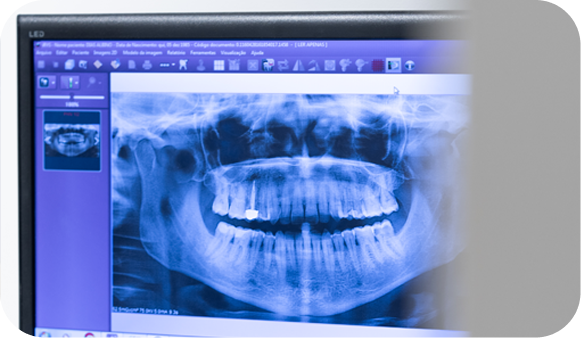

Consulta Inicial

Avaliação clínica e radiográfica para diagnóstico detalhado.